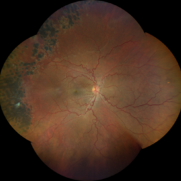

Sickle cell retinopathy (Proliferative) (2 files)

Sickle cell retinopathy (Proliferative) (2 files)

Proliferative sickle retinopathy (1 file)

Proliferative sickle retinopathy (1 file)

Proliferative Sickle Cell Retinopathy (Stage3) (10 files)

Proliferative Sickle Cell Retinopathy (Stage3) (10 files)

Sickle Cell Retinopathy (11 files)

Sickle Cell Retinopathy (11 files)

Sickle Cell Retinopathy SC (6 files)

Sickle Cell Retinopathy SC (6 files)

Sickle Cell (1 file)